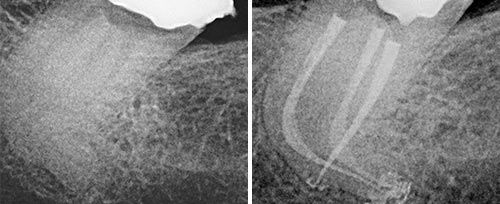

牙髓治疗

牙髓治疗:清洁根管和侧枝根管;深度消毒处理牙本质壁,预防根尖周感染病变。

口腔激光怎么治疗口腔特色诊疗——激光治疗_https://www.jmylbn.com_新闻资讯_第5张

激光辅助根管治疗前后对比图